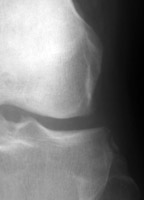

ACL Tear - Segund fracture

Frontal radiographs of the knee which reveal a small fleck of bone adjacent to the lateral aspect of the lateral tibial plateau. This "lateral capsular sign" is a simple radiographic finding visible on the routine AP knee x-ray, which indicates severe lateral capsular injury and should alert the examiner to the possibility of ACL tear. The fleck of bone represents an avulsion of the meniscotibial portion of the middle one-third of the lateral capsular ligament. It most commonly implies a disruption of the capsular ligament and the ACL. A-B Radiographs. C. MRI confirms the diagnosis of ACL tear.

AP knee - Click on the image for a larger versionAAP knee - Click on the image for a larger versionB - Click on the image for a larger versionC